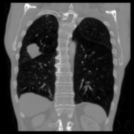

Aside from quantitative results, we provide a principal component analysis (PCA) of the embeddings of Merlin, CT-FM, CT-CLIP, and our COLIPRI encoders, on a lung cancer case from the MSD Lung dataset (Fig. 6).

The resolution of the embeddings of Merlin and CT-FM is very low, providing hardly any localisation of semantics. CT-CLIP yields embeddings of higher resolution, allowing one to map the features from the input chest CT to the PCA map. However, the PCA is inconsistent and noisy, and shows high sensitivity to air in its principal components, and a strong bias towards position embeddings. On the other hand, our COLIPRI encoders yield higher-resolution embeddings, which are sharper and more consistent, allowing for clear recognition of the boundaries of the patient, lungs, and the abdominal organs, as well as the lung mass present in the right lung (on the left-hand side of the coronal and axial slice views).